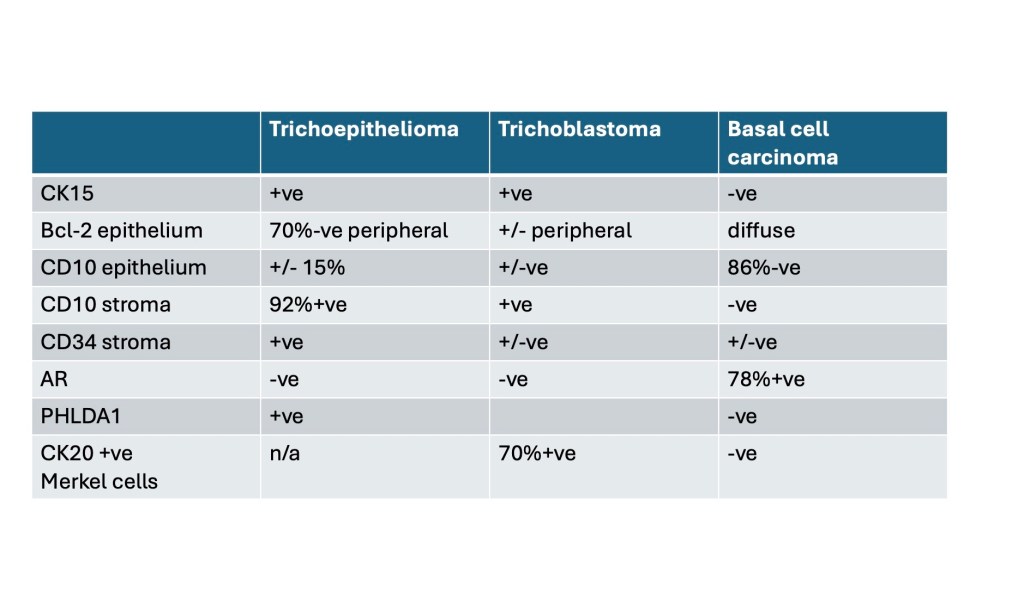

Although the immunohistochemical findings are not always clear cut, points of disctintion are shown in the table.